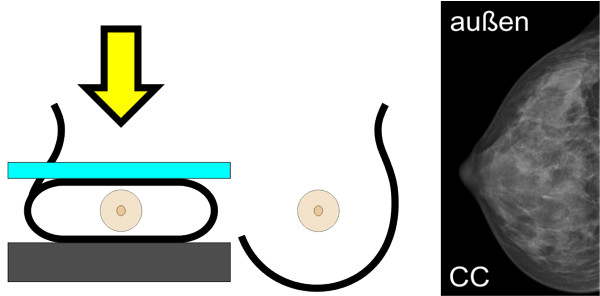

Von jeder Brust werden üblicherweise zwei Aufnahmen - jeweils von oben nach unten (cranio-caudale Aufnahme) und schräg von innen nach außen (medio-laterale oblique Aufnahme) - angefertigt. Die Brust wird dabei in eine Vorrichtung eingespannt und komprimiert:

Die cc-Aufnahme wird immer so dargestellt, dass die Außenseite der Brust im Bild oben liegt.

Viele Frauen empfinden die Druckbelastung durch die Kompression als sehr unangenehm. Unsere Röntgentechnikerinnen sind deshalb speziell darauf geschult, möglichst schonend und behutsam vorzugehen.

Warum ist die Kompression notwendig?

Die Kompression beeinflusst die Qualität der Aufnahme. Je dünner die Brust ausgestrichen ist, desto besser und klarer wird das Bild, wie das Beispiel unten zeigt.

Eine gute Kompression ist für die Qualität der Aufnahme leider unumgänglich. Wir bemühen uns deshalb, möglichst behutsam und schonend vorzugehen.